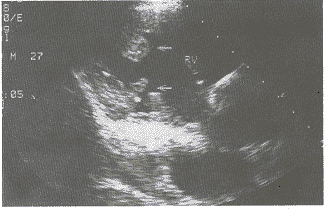

彩超检查所见:右室内径(31mm),右房内径(56×56mm)、均扩大。余房、室径大小正常,房室间隔连续完好,室间隔及左室后壁厚度、运动正常,右房内上腔静脉入口处可探及35mm×16mm的团块状回声,附着面广,回声较均匀,活动较小;三尖瓣后瓣可探及附着于其上的21mm×13mm的团块状回声(图1、2),活动较大,右室前壁中部近乳头肌位置探及团块回声(图3),活动较差。收缩期于右房内探及分布中等的三尖瓣五彩返流束。彩超提示:1、右心占位病变(提示血管肉瘤);2、右房室多发性粘液瘤;3、三尖瓣返流(中度)。

图3 RV内见团块状回声